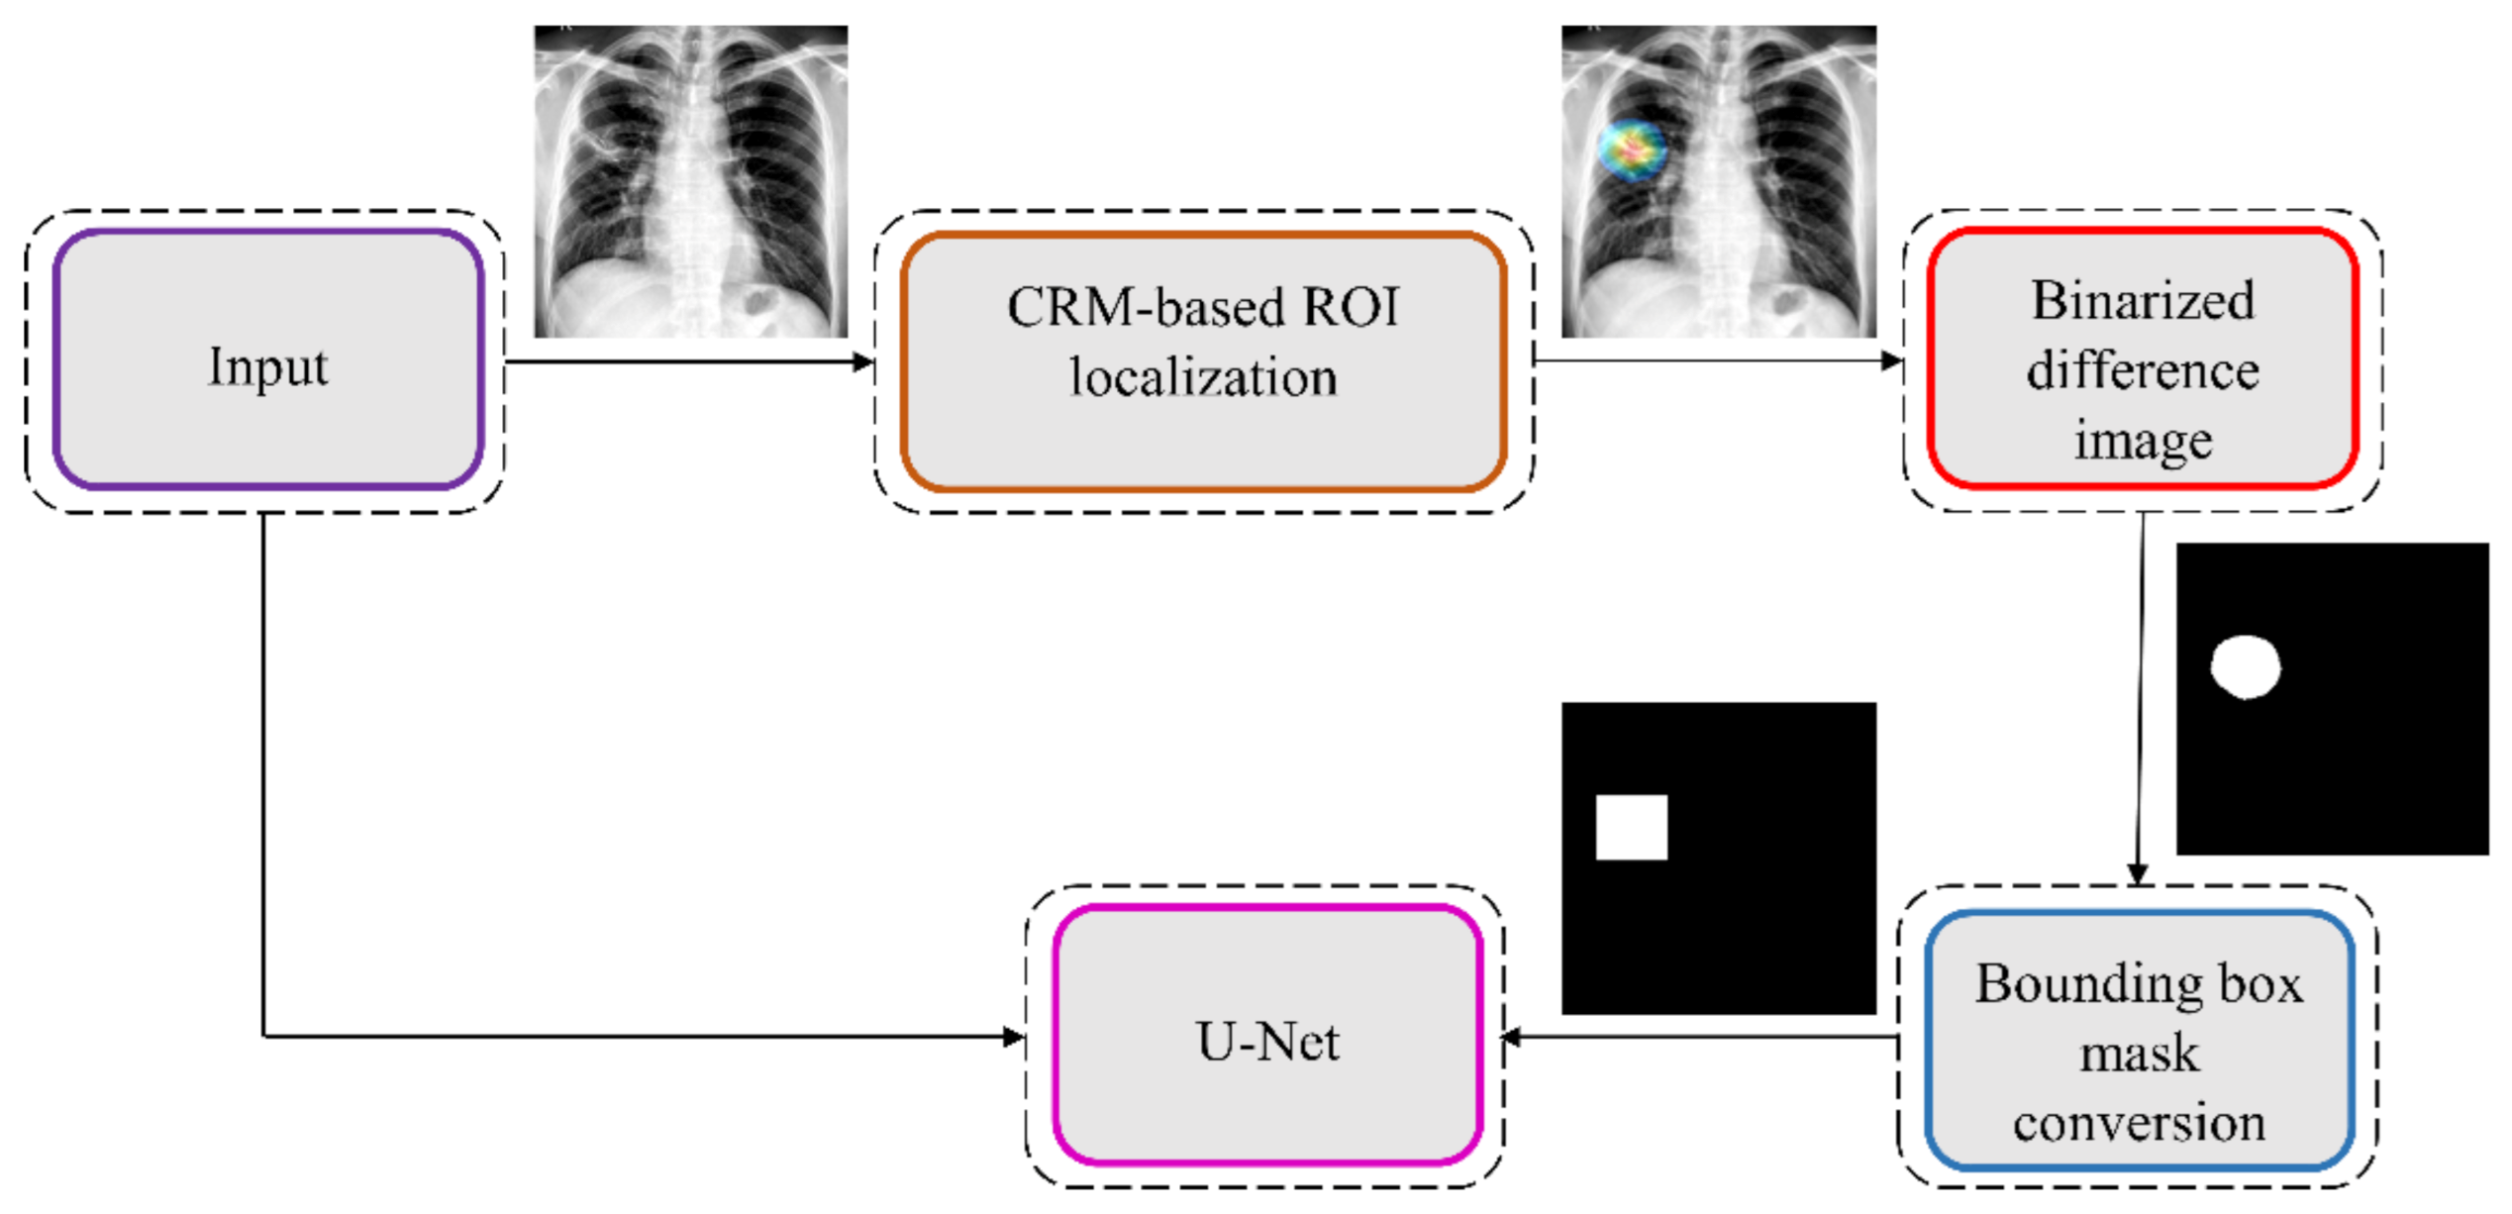

CRM-based visualization algorithms are demonstrated to deliver superior localization performance as compared to the conventional class-activation map (CAM)-based localization, particularly toward medical image analysis [

34]. Unlike CAM-based visualization, CRM-based localization underscores the fact that the feature maps contribute to decreasing the prediction scores for other class categories in addition to increasing the scores for the expected category. Such discrimination helps in maximizing the difference between these scores and results in superior discrimination of class-specific ROI by measuring the incremental mean-squared error from the output nodes. The features are extracted from the deepest convolutional layer of the best-performing fine-tuned model. The CRM algorithm is used to localize the ROI involved in classifying the CXRs as showing pulmonary TB manifestations. The feature map dimensions vary across the models. Hence, the CRMs are upscaled through normalization methods to match the spatial resolution of the input image. The computed CRMs are overlaid on the original image to localize the TB-consistent ROI that is used to categorize the CXRs as showing pulmonary TB manifestations. The CRMs are generated for the CXRs with TB-category labels toward visualizing the regions of TB manifestations. We further converted these CRM-based weak TB-consistent ROI localizations to binary ROI masks. The original CXRs and the associated ROI masks are used for further analysis.

2.10. Task-Appropriate Data Augmentation: Augmenting Training Data with Weak Localizations to Improve TB-Consistent ROI Segmentation

The binary masks obtained from weak TB-consistent ROI localizations using the best-performing fine-tuned model and their associated CXR images are used to perform AT of the models used in

Section 2.7 toward improving TB-consistent ROI segmentation. The performance with such AT is evaluated with the test set derived from TBX11K training distribution and individually with the cross-institutional Shenzhen TB CXR-Subset-2 and Montgomery TB CXR data collections. We used a fixed seed value toward allocating 10% of the training data toward validation. Variability is introduced into the training process by augmenting the training data through affine transformations, including horizontal flipping, height and width shifting, and rotations. Callbacks are used to store model checkpoints, and the best performing model is used to segment TB-consistent manifestations. The predicted masks are overlaid on the original CXR input to localize the TB-consistent ROI boundaries. The performance of the models with AT is evaluated and compared to those with non-augmented training using confusion matrix, IOU, Dice, and AP@[0.5:0.95] metrics. We used a Windows